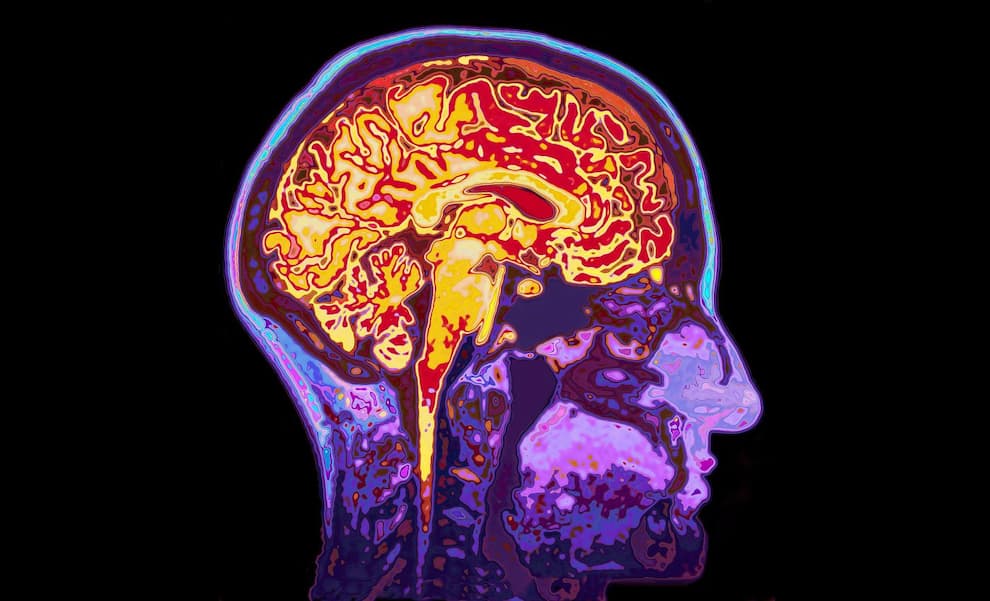

تجمع میکروپلاستیک در مغز انسان؛ زنگ خطر برای سلامت مغز

تجمع میکروپلاستیک در مغز

مطالعه‌ای نگران‌کننده درباره تجمع میکروپلاستیک در مغز انسان نشان می‌دهد ذرات ریز پلاستیکی می‌توانند از سد خونی-مغزی عبور کنند، در نواحی عمقی مغز انباشته شوند. این یافته به‌ویژه در بیماران مبتلا به زوال عقل پررنگ‌تر بوده است.

میکروپلاستیک‌ها، قطعات بسیار کوچک پلاستیک هستند که پیش‌تر در هوا، آب، مواد غذایی شناسایی شده بودند. اکنون شواهد جدید نشان می‌دهد این ذرات به بافت مغز نیز راه پیدا می‌کنند. پرسش اصلی این است: آیا این تجمع می‌تواند عملکرد مغز را مختل کند؟

در این پژوهش، ۵۲ نمونه مغز اهدایی انسان بررسی شد. نتایج نشان داد در تمامی نمونه‌ها ردپای پلی‌اتیلن، سایر پلیمرهای مصنوعی وجود دارد.

• غلظت میکروپلاستیک در نمونه‌های سال ۲۰۲۴ بیشتر از سال ۲۰۱۶ بود.

• روند افزایشی نشان‌دهنده رشد مداوم آلودگی پلاستیکی جهانی است.

• ذرات در نواحی عمقی مغز، از جمله قشر پیشانی مشاهده شدند.

این مطالعه تحت هدایت متیو کمپن، استاد سم‌شناسی دانشگاه نیومکزیکو انجام شد. او با احتیاط درباره نتایج سخن گفت، رشد تولید جهانی پلاستیک را عامل کلیدی دانست.

میکروپلاستیک در مغز بیماران دمانس

بخش قابل‌توجه تحقیق مربوط به مغز بیماران مبتلا به زوال عقل بود. در این گروه، میزان تجمع میکروپلاستیک در مغز سه تا پنج برابر بیشتر از سایر نمونه‌ها گزارش شد.

مشاهده زیر میکروسکوپ الکترونی نیز غافلگیرکننده بود. بسیاری از ذرات به شکل ورقه‌های نامنظم، لبه‌دار دیده شدند، نه کروی و صاف. این ساختار ناهموار می‌تواند تعامل متفاوتی با سلول‌های عصبی داشته باشد.